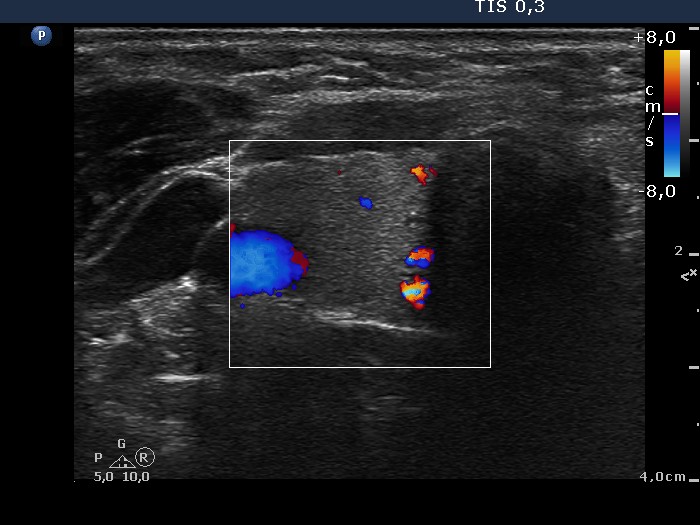

Thyroid cancers - case conp 013 (ultrasonographic picture 3)

Right lobe, longitudinal scan

Right lobe, transverse scan, color Doppler mode. The vascularization is not specific.